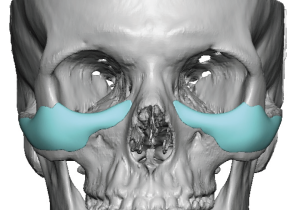

3. Inferior Extension

- Extends below the infraorbital rim while avoiding the infraorbital nerve

- Positioned more laterally relative to the nerve

- Provides vertical support at the lid–cheek junction

- Softens the transition from a negative to a more neutral vector

4. Lateral Extension (Zygomatic Transition)

- Blends into the malar eminence

- Prevents a central over-projection or “bulge”

- Ensures a smooth transition into the lateral orbit

- May extend onto the zygomatic arch when needed for continuity